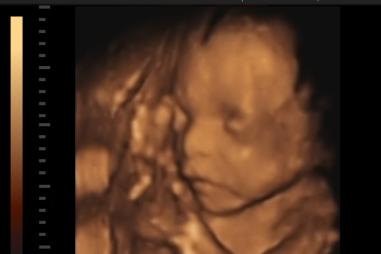

IS-THIS-THE-TRUE-FACE-OF-SAINT-MARY-MAGDALENE-.png

AltKAT

Rekonštrukcia tváre sv. Márie Magdalény - jej lebka v rukách forenzných vedcov ako živá

10.01.2019 undefined

Pomocou pozostatkov, o ktorých Cirkev verí že patria svätej Márii Magdaléne, sa forenzným vedcom podarilo zrekonštruovať tvár ženy, ktorá žila pred dvoma tisícročiami v čase, keď po zemi chodil…